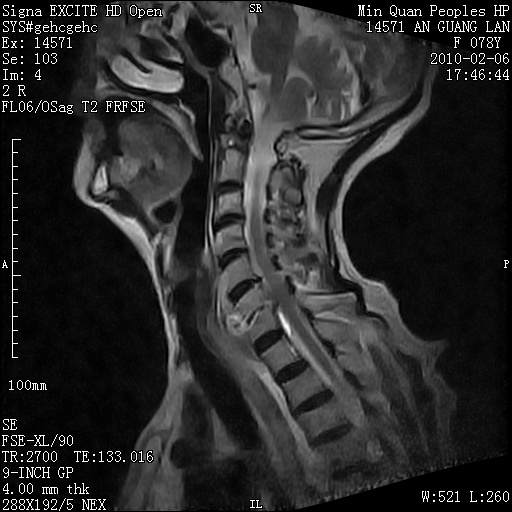

标题: MRI2763:C6、C7椎体病变性质?

f,78y,颈部与双上肢阵发性剧痛40余天。ct可见c6、c7椎体虫蚀样破坏,其间椎间隙变窄(没有图片资料可供上传)。

考虑椎体结核并椎旁脓肿。

支持 c6、7椎体结核并椎旁冷脓肿形成。

考虑:c6/7椎体结核并椎旁脓肿形成,建议增强扫描。